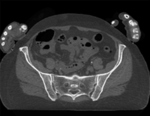

Registration Results

original unregistered unregistered

registered (affine) registered (affine)]

registered (nonrigid w/o masking) registered (nonrigid w/o masking)

registered (nonrigid+masking) registered (nonrigid+masking)

deformation only of vhf registered deformation only of vhf

deformation grid deformation visualized by grid image overlay